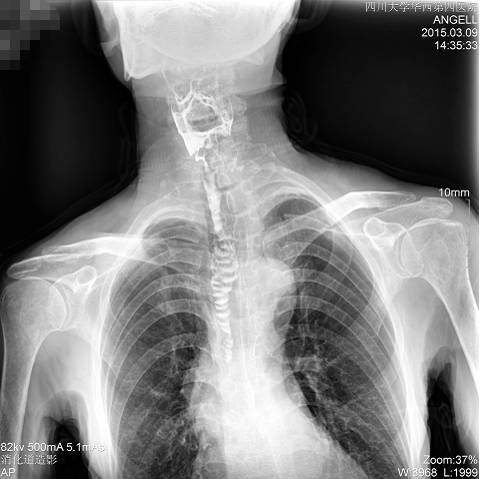

图为正位:通过动态影像可以清楚看到钡剂进入了支气管道且双侧梨状窝不对称

通过多功能dr可以诊断该病人的症状为会厌功能紊乱,钡剂进入到了气管。而在动态透视下可以清晰的观察到钡剂从何处进入气管,可清晰显示食管粘膜结构。使用多功能dr其独特的视频采集技术,可实时保存视频并能实现900万像素实时点片,才能获取这样清晰的病灶点。而常规dr只能拍摄静态片,且成像效果大打折扣,因此较难确诊病灶。